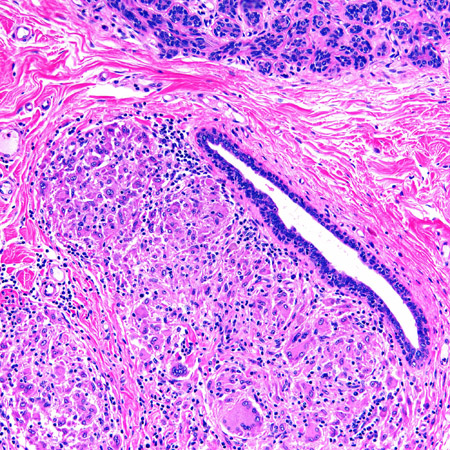

In duct ectasia (dilated ducts associated with inflammation), the mammary duct-associated inflammatory disease sequence involves squamous metaplasia of lactiferous ducts. This causes blockage (obstructive mastopathy) with peri-ductal inflammation and possible duct rupture.[5] Inflamed ducts are prone to bacterial infection. Left untreated, mastitis may cause tissue destruction resulting in an abscess.[Figure caption and citation for the preceding image starts]: Duct ectasia with a central calcified keratin plug and associated giant cell inflammatory responseFrom the collection of Liron Pantanowitz, MD, Tufts University School of Medicine, MA [Citation ends].